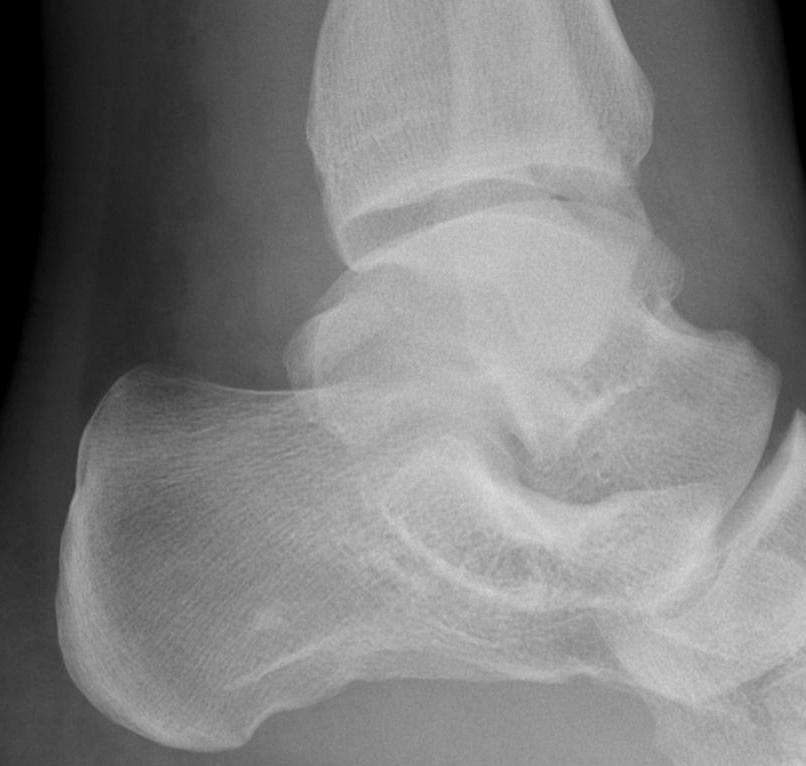

From radiopaedia.org

Posterior talar process fracture Image Talus Bone Fracture Nhs This is a small flake fracture that is treated like a sprain. It is caused by a fragment of bone breaking off (avulsion) from the. How will i know i have broken my. a ‘talus avulsion fracture’ is a small break (fracture) to the ankle bone (talus). the talus bone helps you to transfer weight and pressure across. Talus Bone Fracture Nhs.